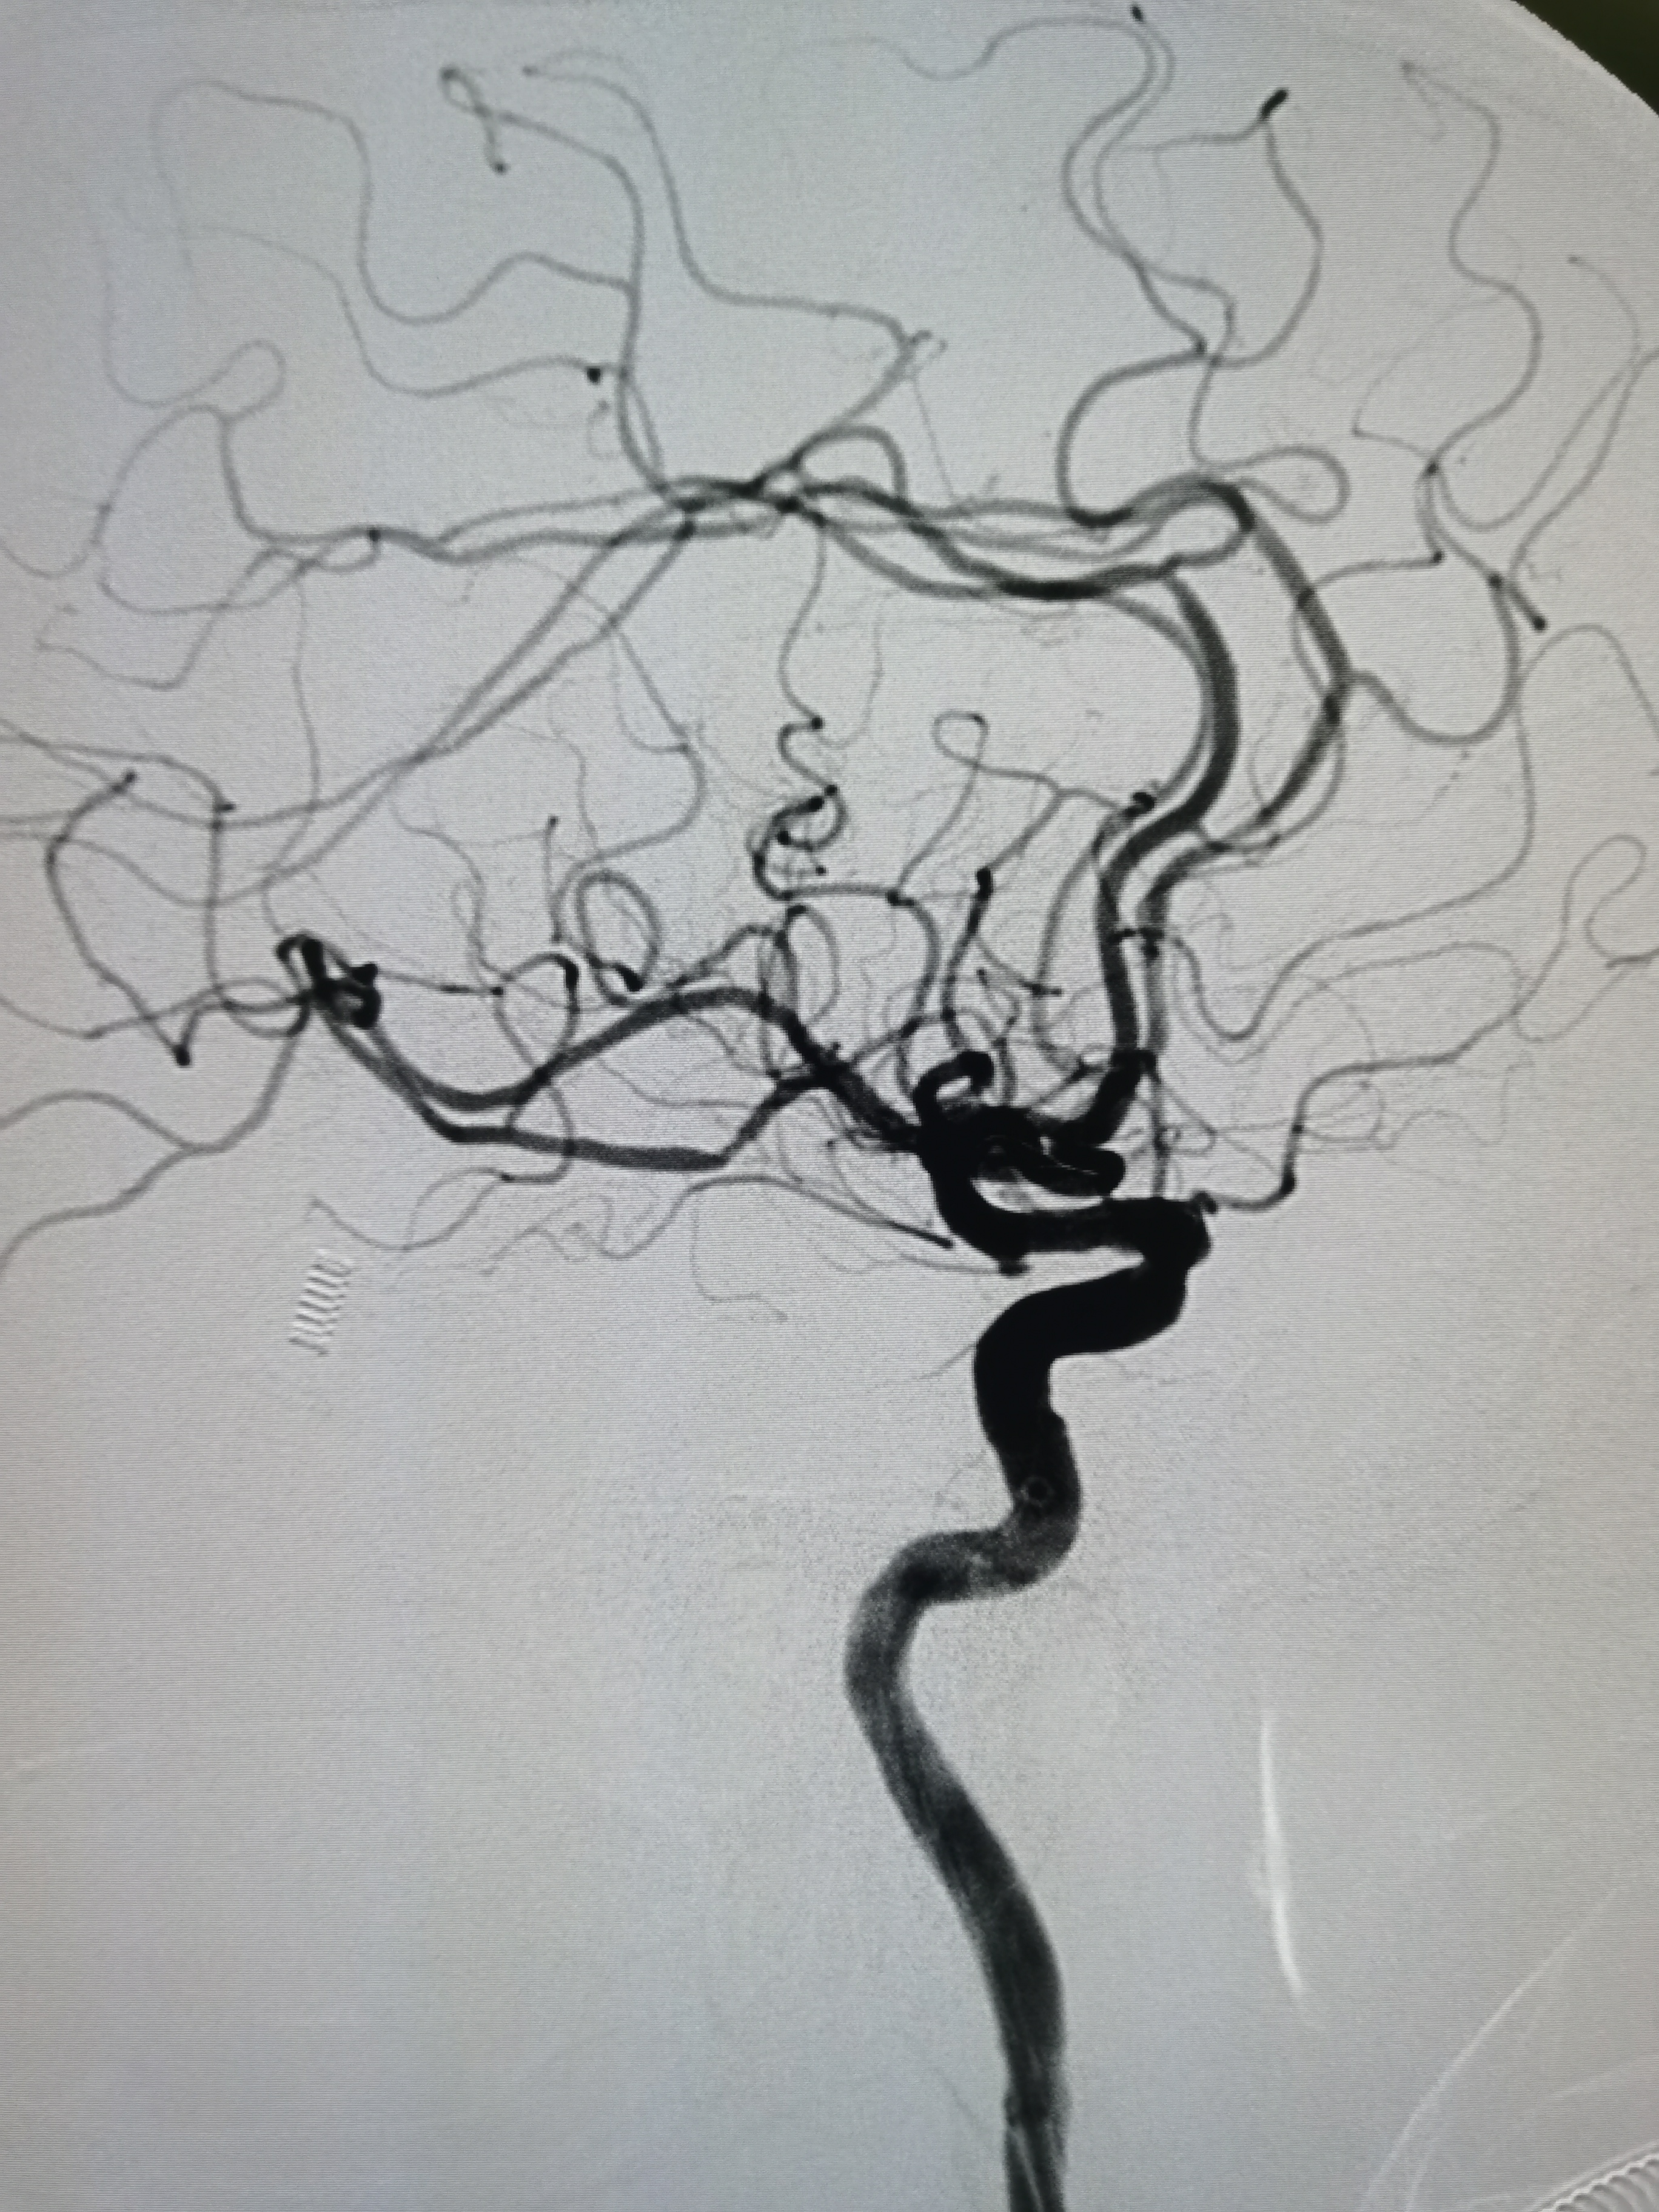

侧位造影见颅内血流通畅。

球囊扩张后狭窄解除,决定不再植入支架,撤出导丝造影见血管通畅,遂逐级撤出各级导管,结束手术。